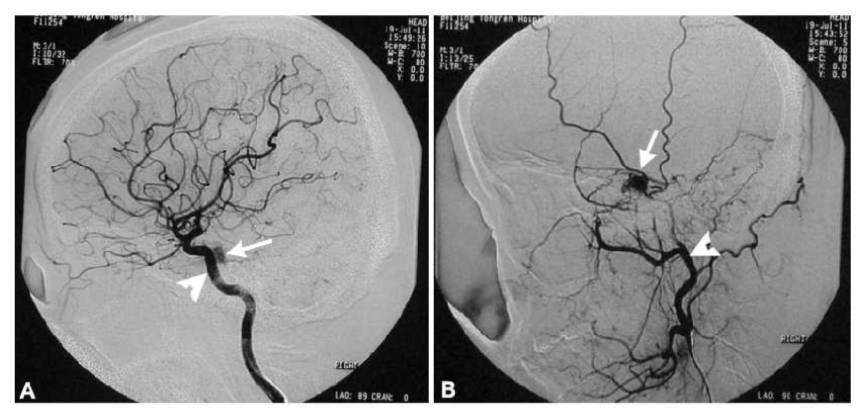

在低流量CCF中,常见海绵窦硬脑膜动静脉畸形,患者眼部症状较隐匿,但有逐渐加重的趋势(图5,图6)。影像学检查MR血管造影及介入导管脑血管DSA有助于确诊且行栓塞手术。

图6.患者脑血管DSA示:(A):海面窦段颈内动脉(白箭头)旁少量造影剂充盈(白箭);(B):颈外动脉与硬脑膜形成交通,造影剂异常渗漏(白箭),白箭头示正常颈内动脉。 (6)外伤性及医源性:外伤可导致海绵窦瘘及其他颅神经损害;蝶窦窥镜手术亦可造成损伤。